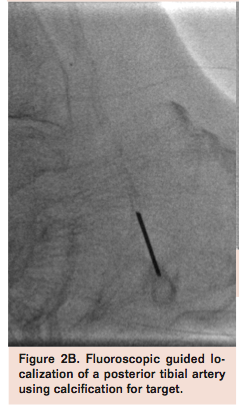

Transpedal access can be performed under direct ultrasound, fluoroscopic, and angiographic or roadmap guidance (Figure 2). A handheld duplex ultrasound can generally identify the desired pedal vessel for puncture.

It is important to recognize the vessel in both long- and short-axis views to avoid venous puncture. Compression sonography helps identify the pulsatile artery from the adjacent vein, although Doppler interrogation may be used when arterial pressure is markedly diminished to ascertain which structure represents the pedal artery. When viewed in short axis, the artery is usually flanked by the accompanying vein on both sides (Figure 2A). In general, if wire passage is free and smooth, one should inject a small amount of contrast to confirm arterial vs venous access. In a heavily calcified pedal vessel one can perform the pedal puncture under direct fluoroscopic guidance (Figure 2B).